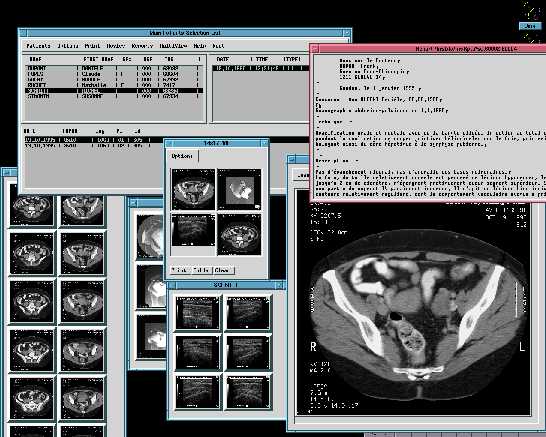

Esto es lo que dije a un amigo suizo que me llamo aqui en España, este explotaba Solaris, X11R4 y Motif 1.1 para los PC's, cada licencia le costaba la bagatela de 8.000 dolares y estaba buscando algo "mas barato", le comente el coste de Linux, no me colgo el telefono porque me tiene aprecio, pero si que me dijo algo que sonaba a "borracho", el caso es que lo compro. Este buen hombre posee una empressa (DAPSYS. SA ) dedicada a la informatica hospitalaria, su especilidad es el archivado de imagenes radiologicas y su restitucion en pantalla, sea con X11 y Motif o Win95.

Esta empresa tenia unas pocas instalaciones ya realizadas en Suiza, cuando de Canada se les presento un dia (casi sin avisar) dos vendedores de una muy importante empresa americana, estos no venian a vender sino comprobar "algo" que "alguien" les habia comentado en el RSNA de Chicago, el RSNA es el evento mundial en el tema de la radiologia. Dos meses despues el director de Dapsys se fue hacia Montreal con su "portatil" para enseñar el producto a unos cuantos doctores, tres meses despues (y 504 años despues de Colon) llego yo a las Americas para hacer la primera instalacion en aquel continente de Iris. Iris es la aplicacion de archivado y restitucion de imagenes radiologicas.

Ademas Iris permite centralizar por paciente TODOS los eventos radiologicos, cada imagen tiene grabada en ella el nombre, apellidos y codigo de paciente, Iris es capaz, mediante tratamiento OCR, extaer esos datos de la imagen y archivar la o las imagenes del paciente junto a las existentes (de haberlas).

Para un paciente determinado se pueden presentar X exploraciones de varias modalidades. Una exploracion es un examen radiologico, un examen puede tener una o X imagenes o disparos. Una modalidad es un aparato capaz de producir imagenes radiologicas sea por Rayos-X, ultrasonidos, resonancia magnetica, etc...

Cuando se producen las imagenes estas llegan directamente al servidor, este tiene que ser capaz de "leer" la imagen y extraer los datos del paciente, para reenviar "rebotar" la imagen a las estaciones de visualizacion y archivar con los datos del paciente leido, para poder devolver la o las imagenes en peticiones posteriores.

Segun las pruebas realizadas una imagen de 512x512x2 tarda 0.3 segundos, de promedio, en mostrarse en pantalla desde que se inicio la transaccion. Hablo de promedio, porque un estudio no es siempre una sola imagen, este promedio es mejorable y no solo por hard sino por la propia forma de obtenerlo.

St.John tiene 12 salas que suelen producir unas 1.000 imagenes al dia, esto da un poco a que se tienen que esperar los dos servidores, durante el periodo de pruebas estamos llegando a la friolera ocupacion de CPU del 2%, con 6 salas enviando imagenes.

Las estaciones de trabajo IRIS/Motif son para hacer una labor de, principalmente, de visualizacion con diagnostico, gracias que pueden pilotar hasta cuatro pantallas, de momento solo tienen 2 de 20 pulgadas, las busquedas en la base de datos se pueden resumir en :

• - Por datos del paciente

• - Fecha de examen, nacimiento

• - Modalidad

• - Patologia

• - Palabra clave